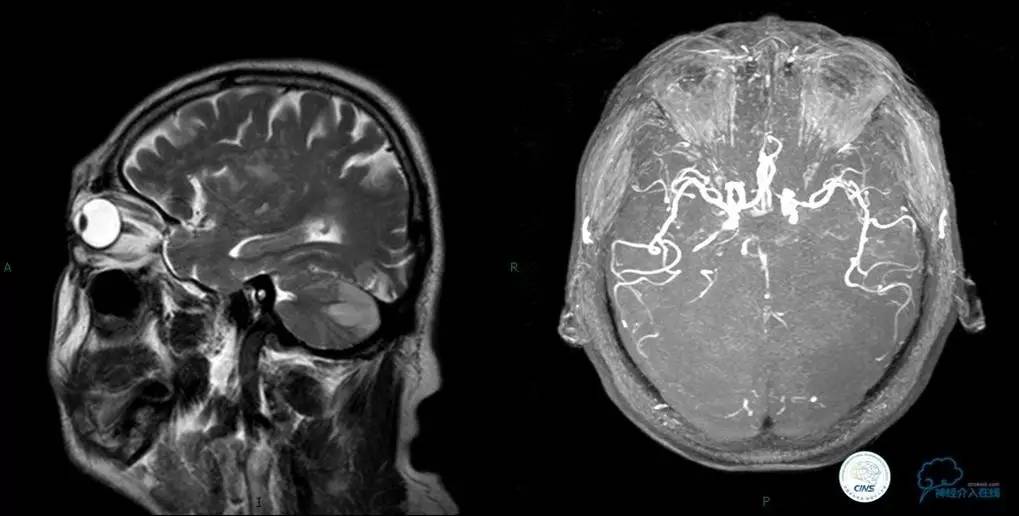

▼头颅MR

术前DSA

▼入院MR